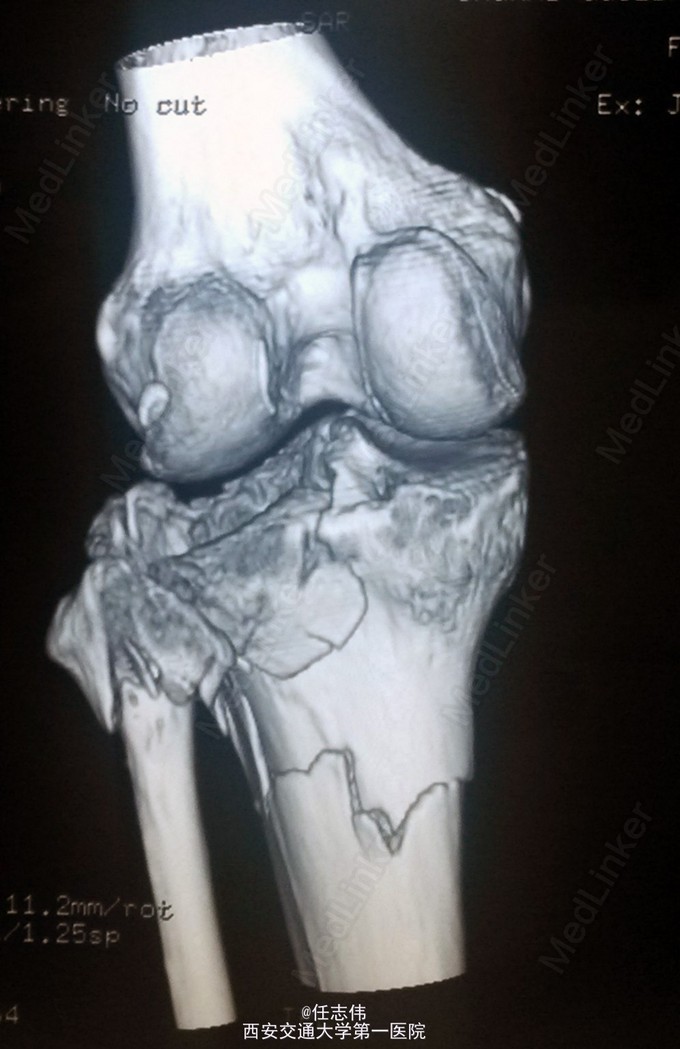

女性,66岁,摔伤致左膝部疼痛活动受限7天 7天前摔伤致左膝部疼痛伴活动受限,在当地医院行跟骨牵引、消肿对症治疗7天,已基本消肿,足部感觉、活动、血供正常。 既往有糖尿病史。

左膝关节周围肿胀,胫骨平台处压痛明显,外侧为著,膝关节活动受限。左足背动脉搏动好,踝及足趾感觉活动正常。

诊断:右胫骨平台骨折 处理:骨折切开复位内固定术。行内外侧入路钢板固定,术中行外侧平台塌陷复位,髂骨植骨内固定。另因考虑有后柱骨折,遂行后外侧切口,支撑钢板固定。术中见患者骨质疏松明显。 术后伤口愈合好,局部仍肿胀明显。

有几个问题想问问: 1.这个是胫骨平台骨折吗?还是胫骨近端骨折伴有平台骨折。 2.手术处理上有什么建议?可以不处理后侧柱吗? 3.大家在复位塌陷平台上有和经验?